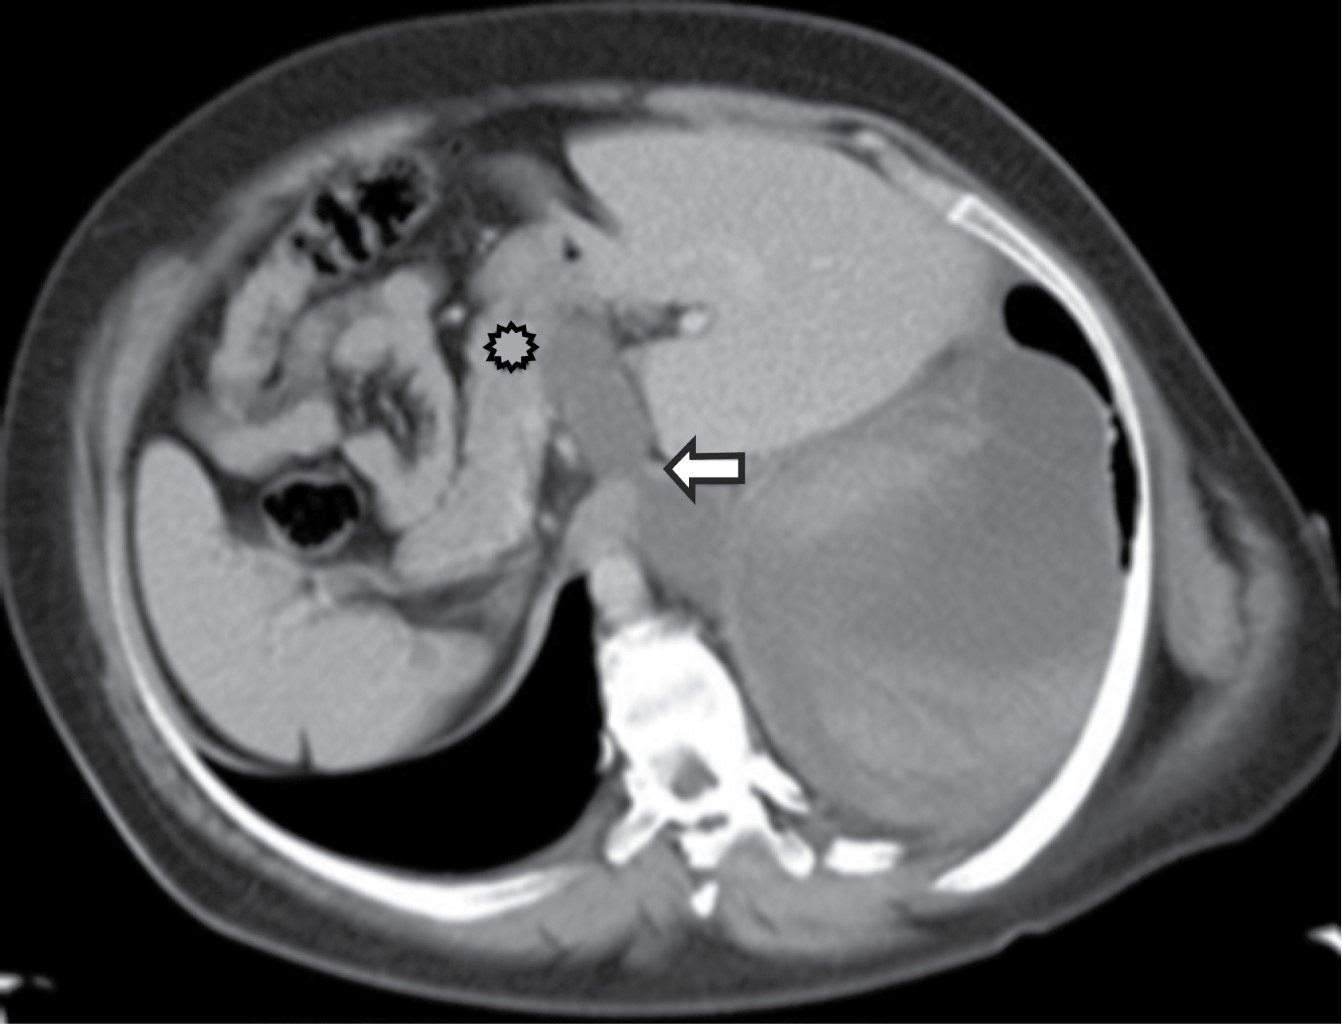

El alcoholismo es un factor común en adultos y en los niños es trauma. En muchos casos, el pseudoquiste se extiende del páncreas al mediastino posterior a través del hiato esofágico. Menos común, puede penetrar a través del hiato aórtico, foramen de Morgagni o una erosión diafragmática.

Representa una colección encapsulada de secreciones pancreáticas, sangre y material necrótico. Siempre ocurre en la parte inferior de mediastino posterior, ganando acceso del tórax por la vía de hiato esofágico o aórtico. La tomografía muestra un quiste de pared delgada, baja atenuación en el mediastino posterior o adyacente a la cavidad torácica asociado con compresión o desplazamiento del esófago, pueden ser hiperatenuantes dependiendo de si hay hemorragia o infección (Figura 12).